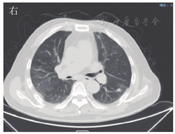

患者男,63岁,因"间断发热1年"于2020年6月29日入河南大学人民医院。患者1年前无明显诱因下出现发热,体温最高达38.0 ℃,伴有反应迟钝、吞咽困难、饮水呛咳、颈部硬肿,无咳嗽、咳痰,无胸闷、呼吸困难。患者于外院查血常规示感染相关指标高,CT检查示颅内感染可能(具体不详),予"美罗培南、万古霉素"抗感染治疗,体温可降至正常,但很快反复;后多次因"颅内感染"住院,予抗感染治疗,疗效差。4月余前因颅内高压、脑积水于外院行脑室-腹腔分流术。3月21日外院头颅MRI检查示左侧枕部颅板下积液、左侧颞枕顶叶明显水肿,增强后明显强化;颅脑术后改变。5月21日肺部CT检查示双肺多发结节影、条索影,考虑慢性炎症。为求进一步诊治来河南大学人民医院,门诊以"发热待查:颅内感染?脑室-腹腔分流术后"收入感染科。患者自发病来,神志欠清,精神差,食欲及睡眠可,二便正常,体质量较前无明显减轻。既往史:2003年因颈椎破坏行植骨术;2013年因"发热伴头痛"发现颅内病变,曾就诊于多家医院均未明确诊断,病情缓慢进展;2018年因"头痛加重"行颅内病变切除术,术后考虑感染性病变,间断抗感染治疗,病情仍无改善。体格检查:体温为36.8 ℃,脉搏为88次/min,呼吸为20次/min,血压为135/85 mmHg(1 mmHg=0.133 kPa)。神志欠清,反应迟钝,对答欠切题,计算力下降。双侧额纹变浅,闭目力差,双侧鼓腮力、咀嚼力差;伸舌困难,舌不能完全伸出;双侧瞳孔等大等圆,眼球活动度差,尤其上视、右视时明显,对光反射迟钝,视力下降;颈部红肿、僵硬,无压痛;双肺听诊呼吸音清,未闻及干、湿啰音;心前区无隆起,心界不大,律齐,各瓣膜听诊区未闻及心脏杂音及心包摩擦音;腹部平软,无压痛,肝脾肋下未及,移动性浊音阴性,肠鸣音正常;双下肢无水肿,肌力3级,腱反射(-),病理征(+)。考虑为免疫性疾病,予补液、营养支持等对症治疗。实验室检查:IgG为37 910 mg/L,抗髓过氧化物酶抗体为24.21 RU/mL,IgE为208.3 IU/mL,IgG4为10 400 mg/L;IL-6为115.88 ng/L;ESR为106 mm/1 h;CRP为146.36 mg/L;降钙素原为0.12 μg/L;血常规、尿常规、粪便常规、游离三碘甲腺原氨酸、游离甲状腺素、促甲状腺激素、T.SPOT.TB检测、β-D-葡聚糖试验、半乳甘露聚糖抗原试验、EB病毒DNA、CMV DNA、布鲁菌抗体、肿瘤标志物均阴性。6月30日胸部CT检查示双肺多发结节,见图1。7月2日头颅MRI平扫+增强检查示脑内多发异常信号影;后纵裂池处脑膜、小脑幕及左侧颞部硬脑膜增厚并明显强化;左侧枕叶局部脑穿通畸形形成,见图2。进一步行腰椎穿刺脑脊液检查示单核细胞计数为66×106/L,蛋白质为6.02 g/L,葡萄糖为2.02 mmol/L,氯化物为119.9 mmol/L。考虑为IgG4相关疾病(immunoglobulin-G4 related disease,IgG4-RD)。7月2日请病理科会诊外院术中脑组织病理切片,结果示(左枕)纤维组织增生伴玻璃样变性,局部胶原化,淋巴袖套结构可见,血管周围及硬化间质内见较多淋巴细胞及浆细胞浸润,浆细胞形态成熟,见图3;免疫组织化学染色示纤维及血管周边可见多量IgG4+浆细胞浸润,IgG4+浆细胞约为50~100个/高倍视野,见图4。根据患者检查结果和多科室专家会诊,诊断为IgG4-RD,累及中枢、肺部、皮肤、骨骼。由于患者病变侵犯脑干,有脑水肿、颅内压升高等表现,可能出现呼吸、心跳骤停等严重并发症,与患者家属沟通患者病情。7月10日开始予甲泼尼龙(500 mg,1次/d,静脉滴注)冲击联合丙种球蛋白(20 g,1次/d,静脉滴注)治疗。当天患者眼球转动基本正常,进食无呛咳,意识、反应和言语明显好转,颈部硬肿好转。予静脉滴注甲泼尼龙500 mg 3 d、240 mg 3 d、120 mg 3 d、80 mg 3 d、40 mg 3 d,以及静脉滴注丙种球蛋白20 g (1次/d) 5 d,患者症状明显改善,复查IgG、IgG4、ESR、CRP均较前下降。7月13日肺部CT检查示双肺结节明显缩小,见图5。7月19日头颅MRI检查示颅内局部脑水肿减轻,后纵裂池处脑膜、小脑幕及左侧颞部硬脑膜病变缩小,见图6。患者症状逐渐好转,7月24日患者及家属要求出院。出院后继续予甲泼尼龙治疗,后联合吗替麦考酚酯,患者一般情况稳定,定向力、记忆力、认知力正常,言语流利。